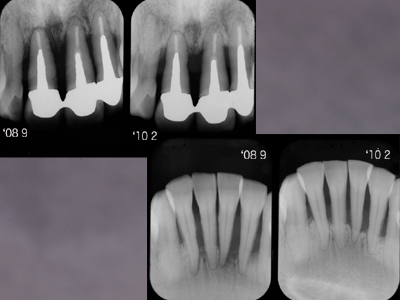

'08 9主治医の紹介で当院に来院されて以来、さすがに熱心にプラークコントロールに取り組んでいただきました。'08 9~'10 2のプロービングデプスの変化です。青は6mm以上、赤はBOPを示しています。

「PD6mm以上は歯周外科」というのがEBMだそうですが、EBMってのもあまりあてにならないことがわかります。そしてこの間の上下前歯部のレントゲン像の変化です。

初診時右上1左下1はすでにに根尖をこえて骨がないようにみえますが、1年半経過し骨が戻ってきました。抜歯の前に当院に来られて本当によかった。